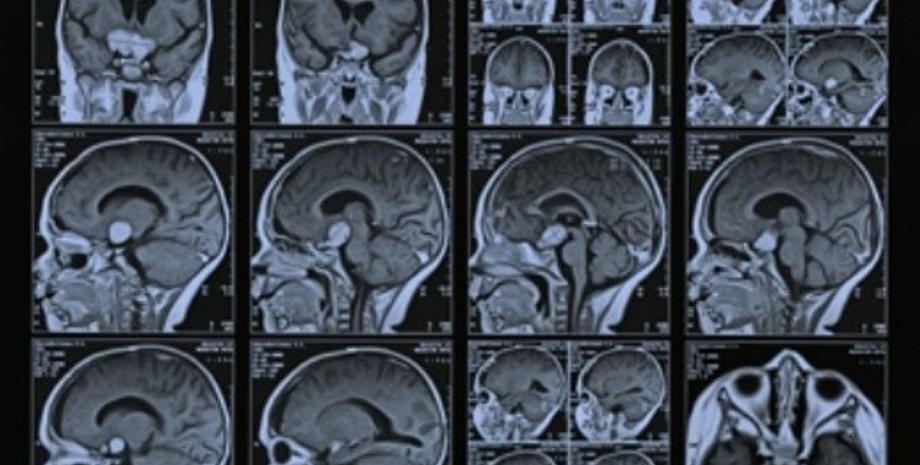

МРТ позволит легко диагностировать аутизм

Диагноз ставится по внешним проявлениям, которых у расстройств аутистического спектра великое множество. Исследователи из Колумбийского университета в Нью-Йорке предложили свой способ однозначной диагностики аутизма, основанный на использовании функциональной МРТ.

Одним из характерных признаков аутистических расстройств является трудность в общении, которая рано или поздно проявляется у ребенка; такие дети редко и плохо говорят и часто словно бы не слышат, что говорят им другие. В исследовании принимали участие 15 здоровых детей и 12 — с нарушениями речи и явными признаками аутизма; в среднем все испытуемые были чуть старше 12 лет. Во время сканирования мозга с помощью томографа им давали слушать запись с речью родителей, которые как бы разговаривали с ними.

У здоровых подопытных в ответ на родительскую речь повышалась активность двух зон мозга — первичной слуховой коры и верхней височной извилины, которая отвечает за понимание предложения как взаимосвязанной последовательности слов. У аутичных детей активность первичной слуховой коры была такой же, как у здоровых, но активность верхней височной извилины оказывалась значительно ниже. Иначе говоря, аутисты с нарушениями речи буквально не понимают, что им говорят, предложение слышится им как набор не связанных между собой слов. Точно так же различалась мозговая активность у здоровых и аутичных детей после приема успокаивающих препаратов: несмотря на действие седативных лекарств, "понимающая язык" извилина по-разному работала у обеих групп.